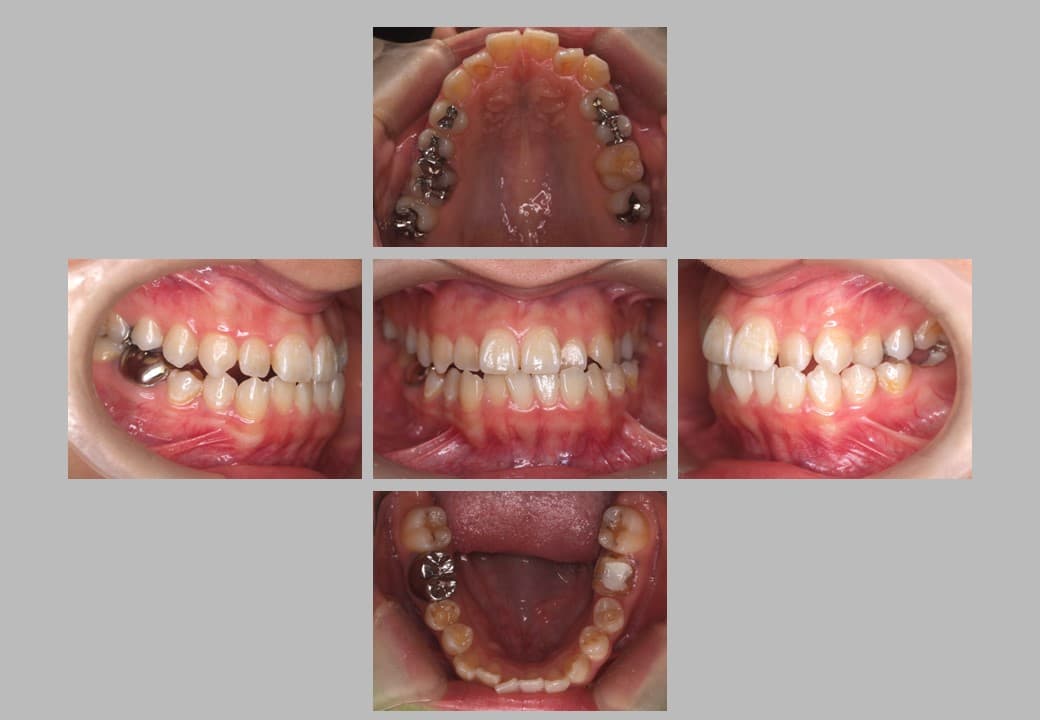

• 治療後